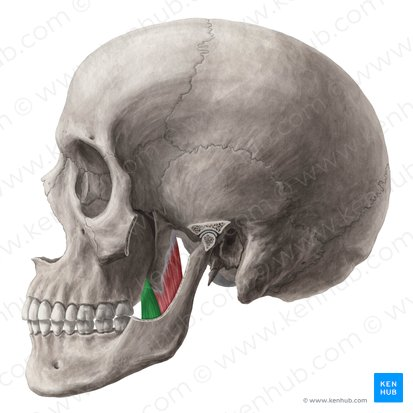

m temporalis

m masseter

m pterigoideus medialis

m pterigoideus lateralis